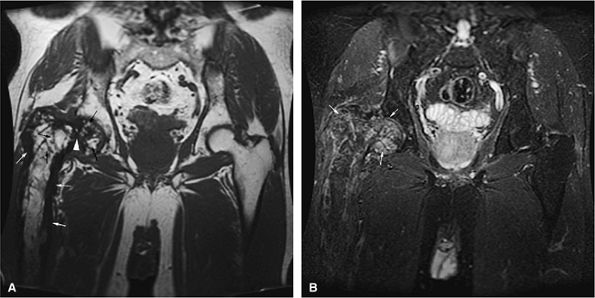

FIGURE 13.18 ● In chronic myelogenous leu-kemia, diffuse marrow involvement infiltrates regions of previous red marrow stores in the femurs (curved arrows) and acetabulum (straight black arrows) and demonstrates low signal intensity on a T1-weighted image (A) and high signal intensity on a corresponding STIR image (B). The sites where yellow marrow is spared (the greater trochanter and femoral epiphysis) demonstrate high signal intensity on the T1-weighted image and low signal intensity (from the nulled fat signal) on the STIR sequence (white arrows).